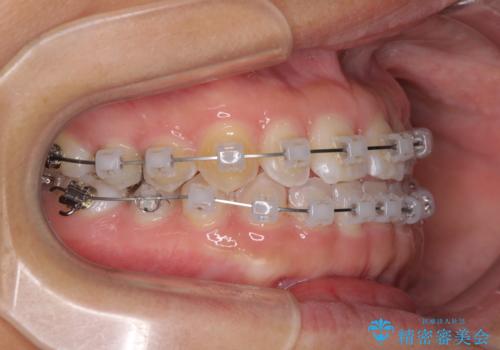

- クリアブラケット

- 9ヶ月

- 5-10回

インビザラインの自己管理は自信がないとのことで、ワイヤー矯正により隙間を閉じていくこととしました。

下の前歯が上の前歯を突き上げるように咬合するため、咬み合わせの位置を改善しながら隙間を閉じていきました。